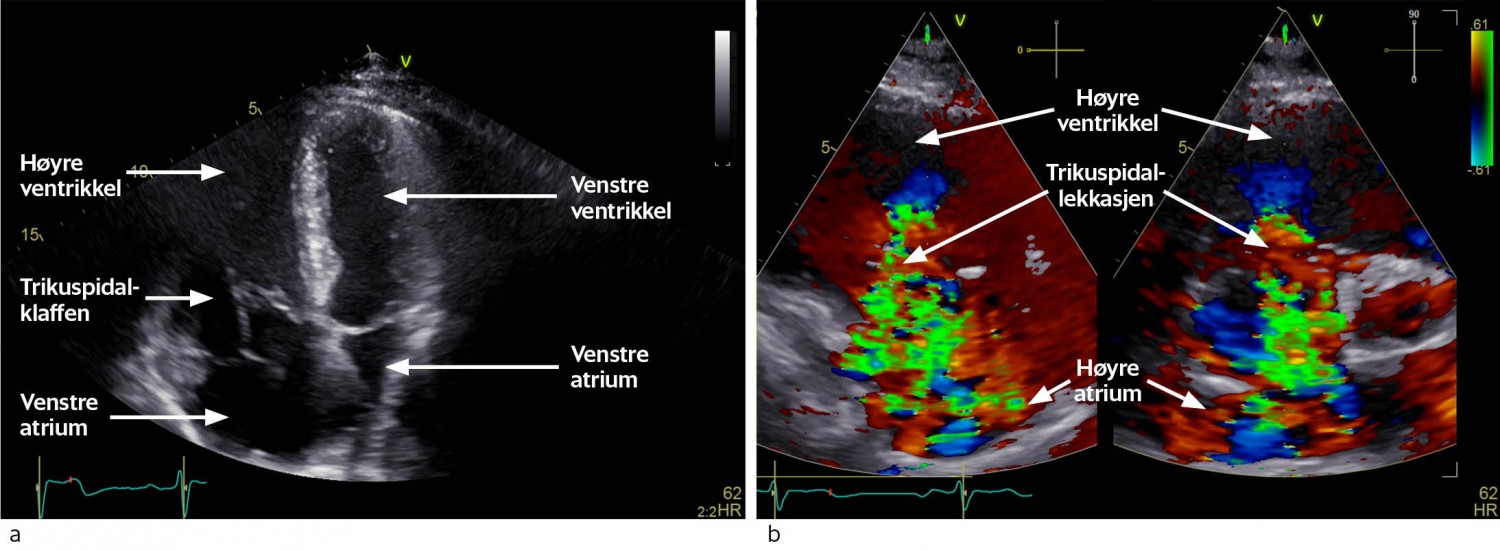

Pasienten kom til hjertemedisinsk utredning ved universitetssykehuset et par måneder senere. Transtorakal og transøsofageal ekkokardiografi bekreftet omfattende trikuspidalpatologi med chordarupturer og prolaps av anteriore segl (figur 1a). Trikuspidalannulus var dilatert, og det var manglende systolisk kontakt mellom klaffeseglene. Dette forårsaket en stor lekkasje (Figur 1b) med systolisk reversering av blodstrøm i levervenene. Vena cava inferior var dilatert og hadde manglende respirasjonsvariasjon, forenlig med høyt høyresidig fylningstrykk. Høyre ventrikkel var dilatert, med normal veggtykkelse og god langaksebevegelse. Høyre atrium var også dilatert. I tillegg hadde pasienten en forholdsvis stor medfødt atrieseptumdefekt i sekundumområdet av atrieseptum (figur 2a og b). Det var ikke ekkokardiografiske holdepunkter for pulmonal hypertensjon.

Atrieseptumdefekter er blant de vanligste medfødte hjertefeilene og forekommer hos ca. 0,5–2 per 1 000 fødte (4). Defektene deles i tre hovedgrupper: sekundumdefekter, primumdefekter og sinus venosus-defekter. Sekundumdefekter er vanligst og skyldes vedvarende fysiologisk atrieforbindelse fra fosterlivet. Konsekvensene av atrieseptumdefekt avhenger hovedsakelig av størrelsen på defekten. Større defekter gir vanligvis symptomer i løpet av livet (4). Grunnet trykkforholdene i hjertet vil blodstrømmen hovedsakelig ha retning fra venstre til høyre atrium (venstre-høyre-shunt). Dette kan forårsake volumbelastning av høyre hjertehalvdel og økt blodstrøm i lungekretsløpet. Vedvarende volumoverbelastning og dilatasjon av høyre hjertehalvdel kan forårsake supraventrikulære arytmier. Høyresidig hjertesvikt og økt blodvolum i lungekretsløpet kan gi symptomer som fatigue, redusert funksjonskapasitet og hyppige pneumonier. I ytterste konsekvens kan det gi leverstuvning med leversvikt, ascites og perifere ødemer. Ekkokardiografi står sentralt i diagnostikken av atrieseptumdefekter. Tegn på signifikant venstre-høyre-shunt er blant annet dilatasjon av høyre atrium, diastolisk avflating eller paradoks bevegelse av ventrikkelseptum og dilatasjon av v. cava inferior (5).

Atrieseptumdefekter gir sjelden vesentlig redusert oksygensaturasjon. Betydningsfull høyre-venstre-shunt kan imidlertid forekomme ved f.eks. høyresidig hjertesvikt eller pulmonal hypertensjon (6). Små pasientmaterialer har også beskrevet at trikuspidalinsuffisiens kan forårsake høyre-venstre-shunting selv om lekkasjen ikke er stor nok til å reversere trykkgradienten mellom høyre og venstre atrium (6). Dette kan forekomme dersom trikuspidalinsuffisiensens retning peker direkte inn mot atrieseptumdefekten.